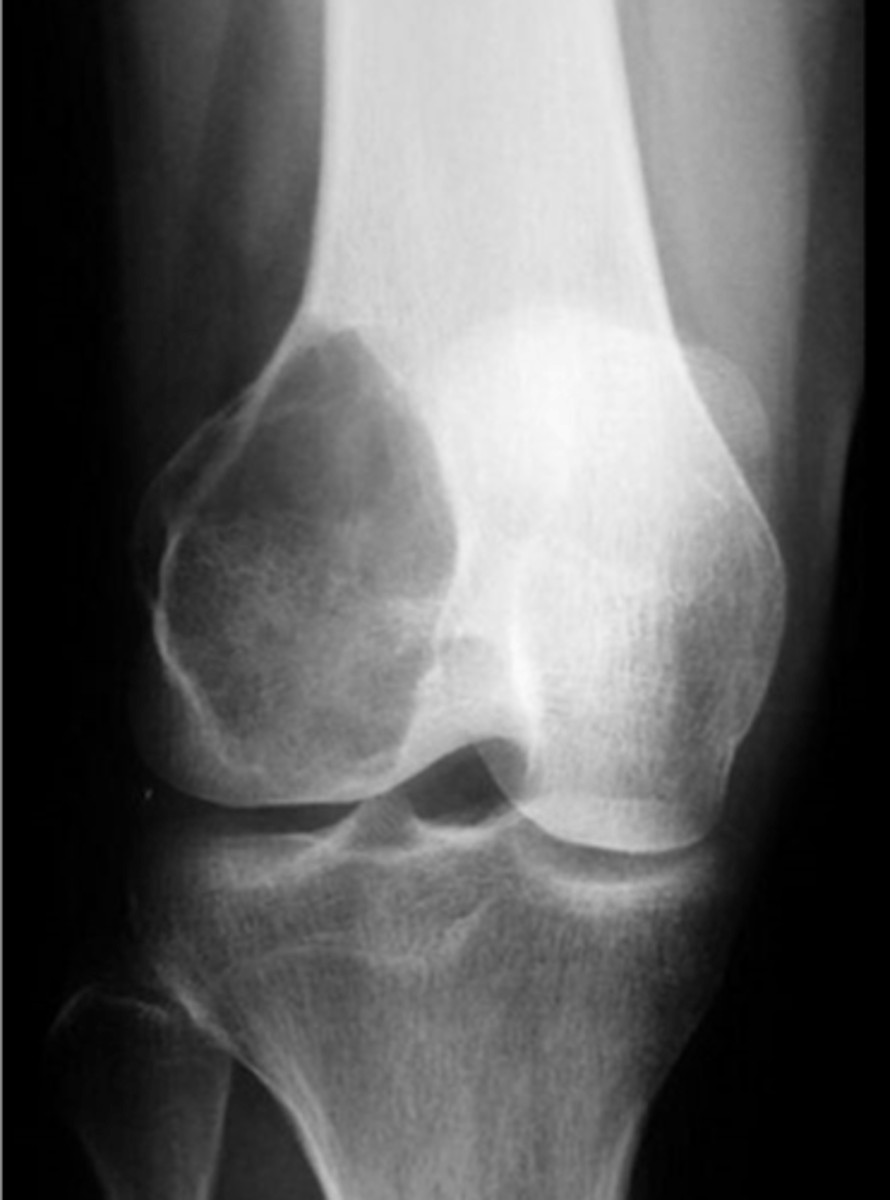

Osteoclastoma

Another term for giant cell tumor

- 80%

- 20%

Giant cell tumor pathology:

- _____ benign (F:M, 3:2)

- _____ malignant (M:F, 3:1)

<p>Giant cell tumor pathology:</p><p>- _____ benign (F:M, 3:2)</p><p>- _____ malignant (M:F, 3:1)</p>

- 20-40 y.o.

- Knee (tibia and femur)

- Localized pain and aching

- Joint pain and restricted motion

State the clinical features of giant cell tumor

- Osteolytic

- Geographic

- Multiloculated and septated

- Begin in metaphysis

- Extend to subarticular bone

- Expansion

- Eccentric

- Quasi-malignant (can't tell benign from malignant)

State the imaging features of giant cell tumor